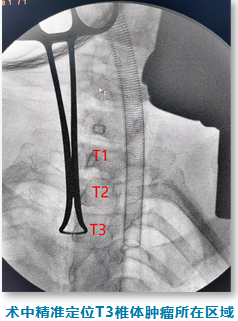

术中,肿瘤与脊髓紧密相连,稍有不慎,很可能导致脊髓的损伤。如果损伤脊髓,手术后陈女士可能再也无法下床行走。刘龙奇在手术显微镜下,抽丝剥茧,精细的分离肿瘤和脊髓,经过近4小时的奋斗,最终在未损伤脊髓的情况下,顺利将肿瘤完整切除。